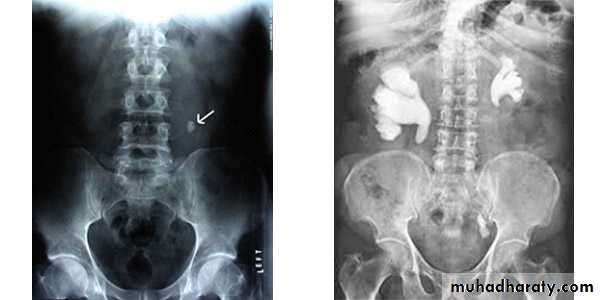

Calcification of the urinary bladder wall

bladder exstrophy

radiographic appearance in bladder exstrophy. It describes wide midline separation of the pubic bones.Bladder exstrophy (also known as ectopia vesicae) refers to a herniation of the urinary bladder through an anterior abdominal wall defect. The severity of these defects is widely variable.